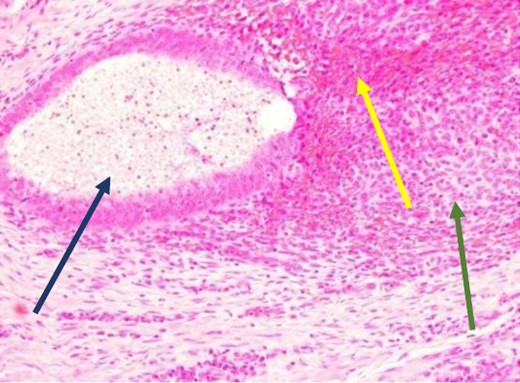

The mass was located in the subcutaneous tissue deep to the previous Pfannenstiel scar but did not invade the anterior rectus fascia. The mass was cleanly separated from the fascia and there was no invasion of the underlying muscle. During dissection, a few areas of the fascia were entered and repaired primarily. Pathology revealed endometriosis within a 4 × 3.5 × 2 cm mass with the closest margin of endometrial-like tissue measuring 2 mm from the specimen edge (Fig. 10a and b). During her postoperative visit 1 month later, the patient complained of some discomfort, yet her cyclical symptoms had resolved.

Proliferative endometrial gland (arrows) and stroma with hemorrhage in the lumen of the gland at 20× (a) and 40× (b) (H&E).